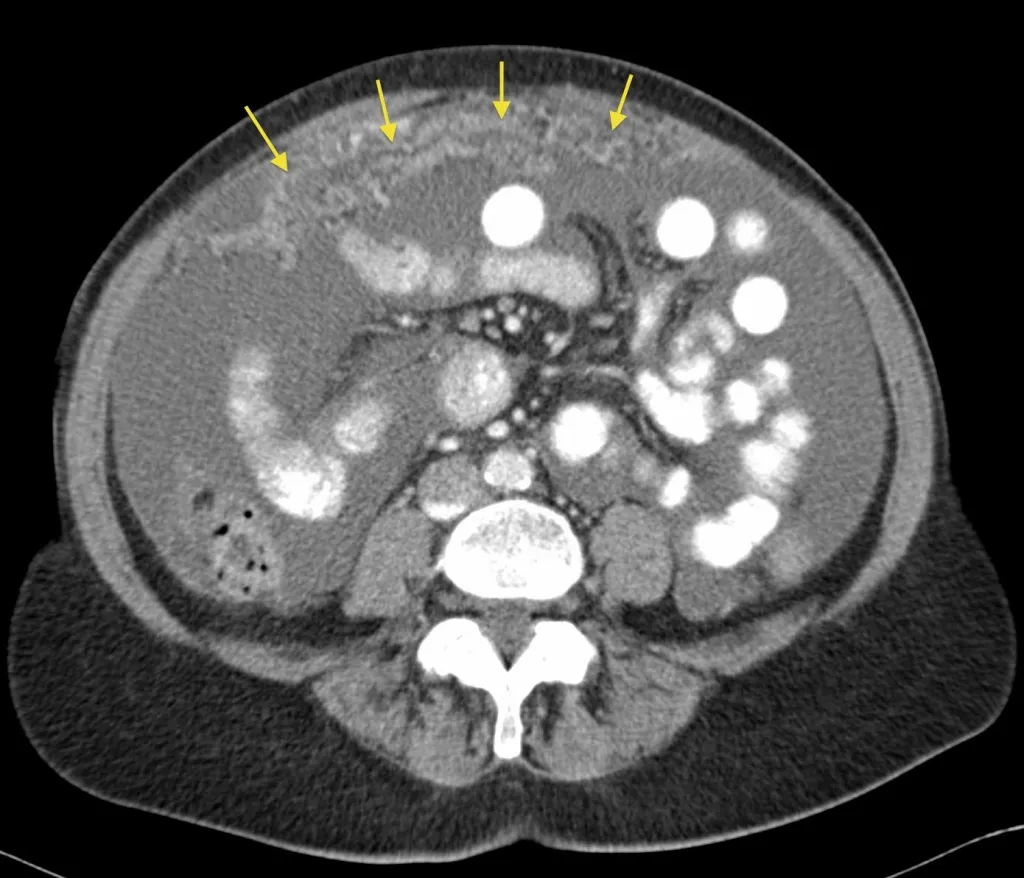

Diagnosis usually arrives through imaging tests showing the abdomen, either by CT scan or MRI, blood tests aiding in detecting some markers, and, conclusively, a biopsy to confirm the spread of cancerous cells.